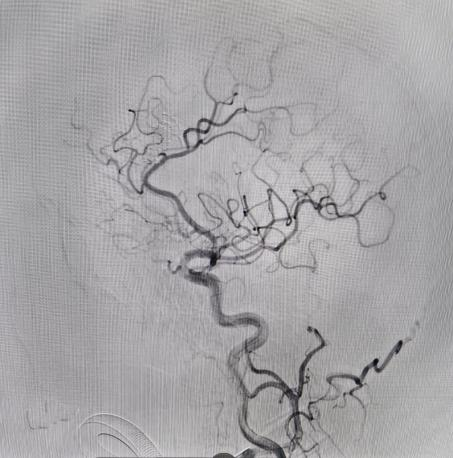

对于非责任动脉瘤的处理,医生们更是展现出专业与耐心。9个月前,患者动脉瘤破裂出血,当时造影发现2处动脉瘤,术中优先处理责任动脉瘤,待患者身体恢复后择期处理非责任动脉瘤。此次处理非责任动脉瘤,手术中造影,发现责任动脉瘤栓塞术后复发(3月前复查尚无),医生们当机立断,同期处理两个动脉瘤,省钱的同时,也成功为患者解除隐患。